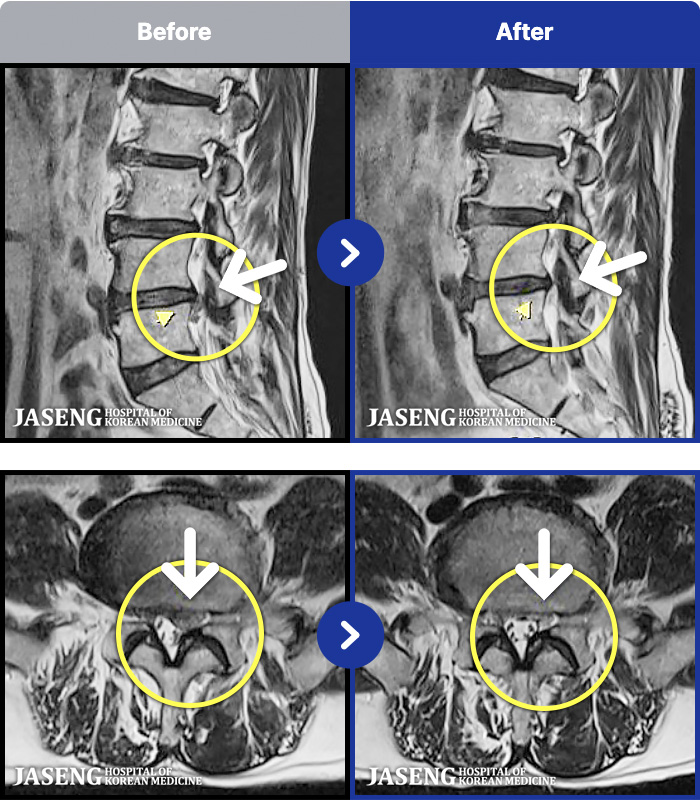

MRI ġ

96 MRI ũ ʸ Ȯϼ.

㸮 ߹ٴڱ ,

ǿ

ȯ

㸮ũ

赿

¥

2019.08.09

[] 18.09.29~19.07.26

ȯںп Ǹ ǿ ԿǾ, ο ġ ۿ Ƿ ġḦ Ͻñ ٶϴ.